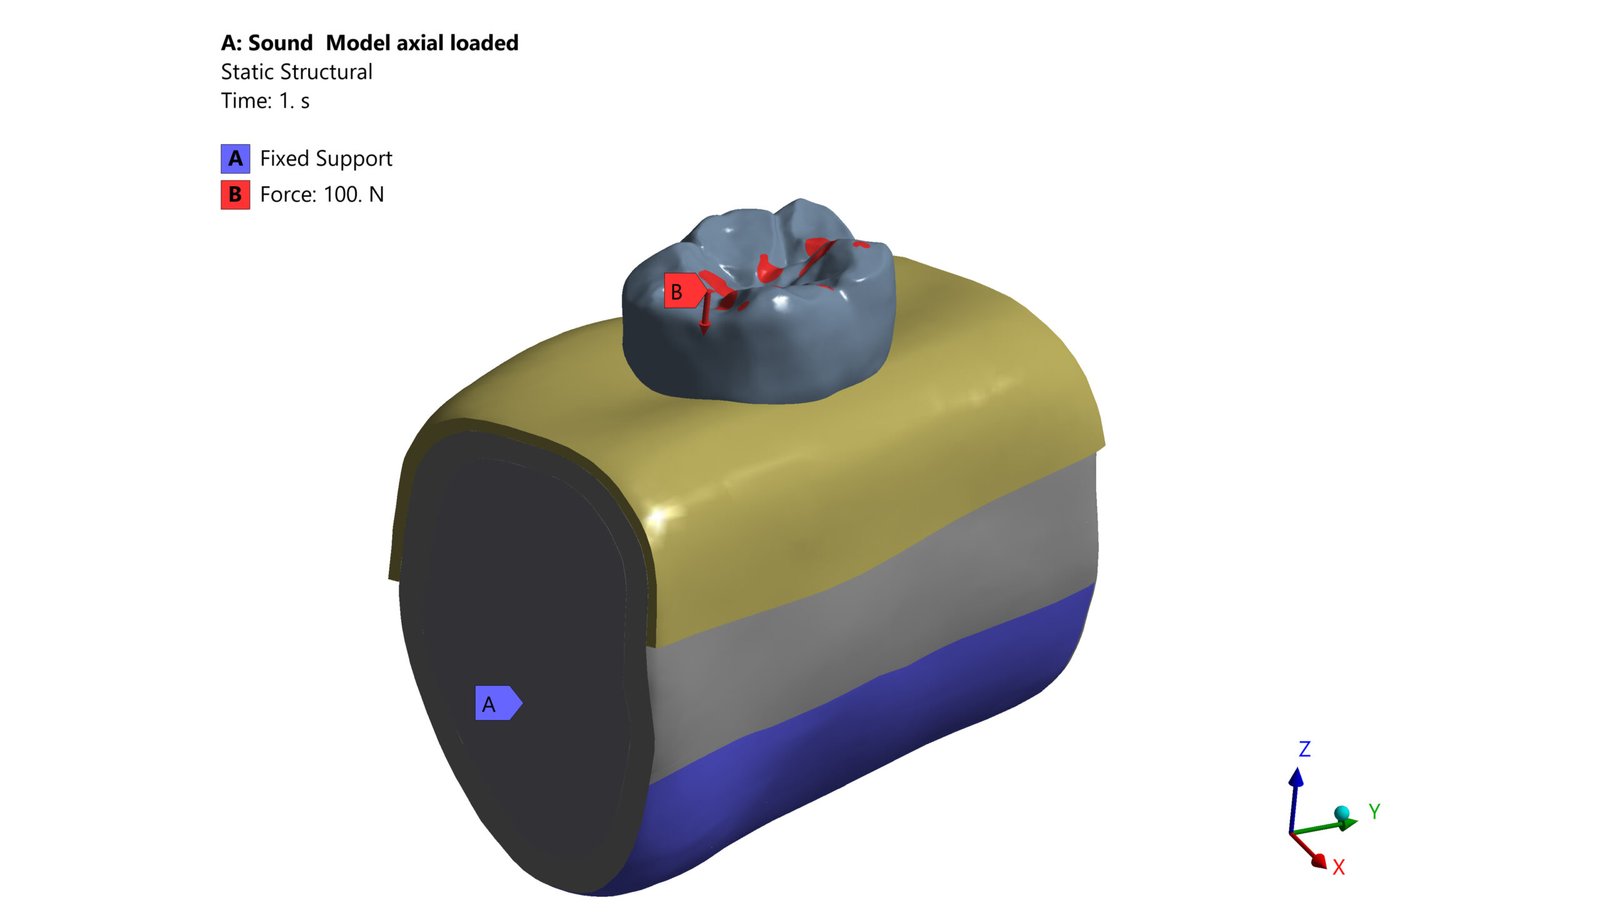

The Endodontic FEA section evaluates the biomechanical performance of root canal–treated teeth, endodontic tools, and reinforcement strategies. Through precise material characterization and micro-CT–based superimposition, we assess fracture risk, stress pathways, and instrument fatigue under various clinical scenarios. These simulations guide the selection of safer instrumentation techniques and restorative strategies. Our goal is to enhance predictability and reduce procedural complications.